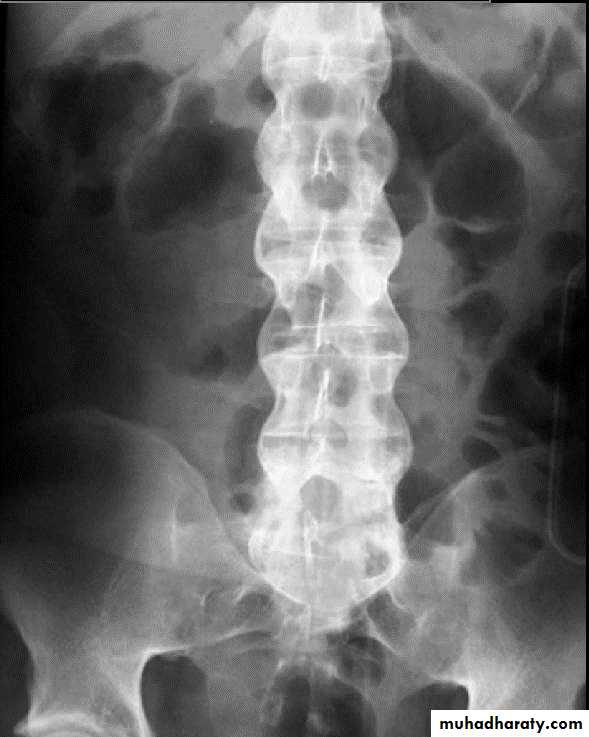

Gibbous deformity wedging of the vertebra (anterior loss of vertebral height)

Seen in TB infection of vertebra

*Bamboo spine (ankylosing spondylitis )

*square shape vertebra (ankylosing spondylits )

Bamboo spine … Ankylosing spondylits

Potts disease also known as tuberculous spondylitis, refers to vertebral body and intervertebral disc involvement with tuberculosis (TB)

Gibbus deformity is a short-segment thoracolumbar kyphosis causing sharp angulation.